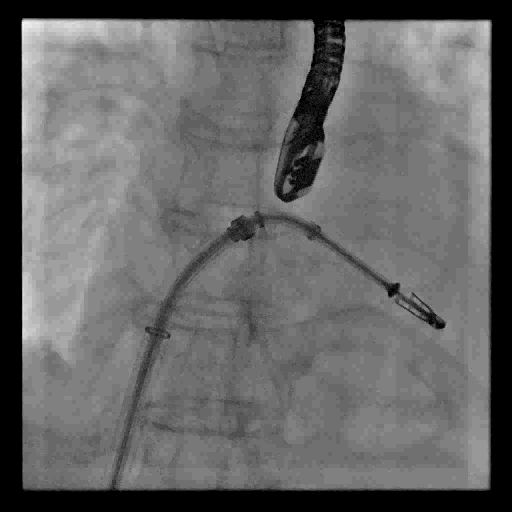

视频3 第一枚MitraClip XTR夹合器在二尖瓣P2区植入,图示夹合器释放过程

视频5 第二枚MitraClip NTR夹合器在P2区第一枚夹合器内侧顺利植入,图示夹合器释放过程

4月11日上午患者在全麻下接受MitraClip经皮二尖瓣夹合术。术中穿刺右股静脉,经食道超声心动图(TEE)再次评估瓣膜病变(视频1),并引导顺利穿刺房间隔(视频2)。随后送入二尖瓣夹合系统,在TEE引导下于二尖瓣P2区植入MitraClip XTR夹合器一枚(视频3),二尖瓣关闭不全减轻,但夹合器内侧仍存在反流(视频4)。团队决定为患者植入第二枚夹合器(MitraClip NTR),手术过程顺利(视频5)。TEE三维显示在植入第二枚NTR夹合器后,二尖瓣呈双孔启闭,两枚夹合器位置、结构正常(视频6)。配备心腔镜功能的TEE三维TrueVue彩色多普勒显示二尖瓣反流将至少量(视频7),且未致二尖瓣口狭窄(图1),夹合效果满意。手术通过视频连线得到香港亚洲心脏病中心主任林逸贤教授的技术支持。